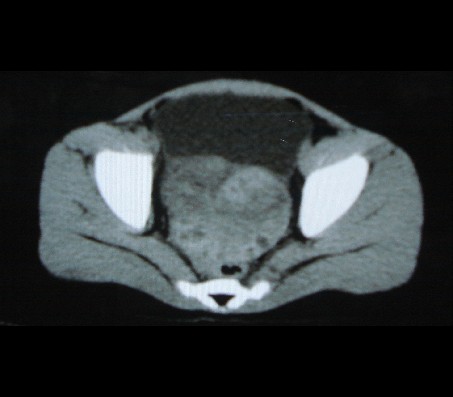

标题: PED0942:女性,8岁,B超提示盆腔病变,请会诊! [打印本页]

标题: PED0942:女性,8岁,B超提示盆腔病变,请会诊!

畸胎瘤

考虑畸胎瘤可能性大!

建议增强进一步检查除外畸胎瘤。

考虑畸胎瘤可能。

考虑畸胎瘤可能

考虑畸胎瘤可能性大.

考虑畸胎瘤可能性大。

畸胎瘤可能性大。

畸胎瘤可能性大!

考虑畸胎瘤可能大,建议进一步检查。